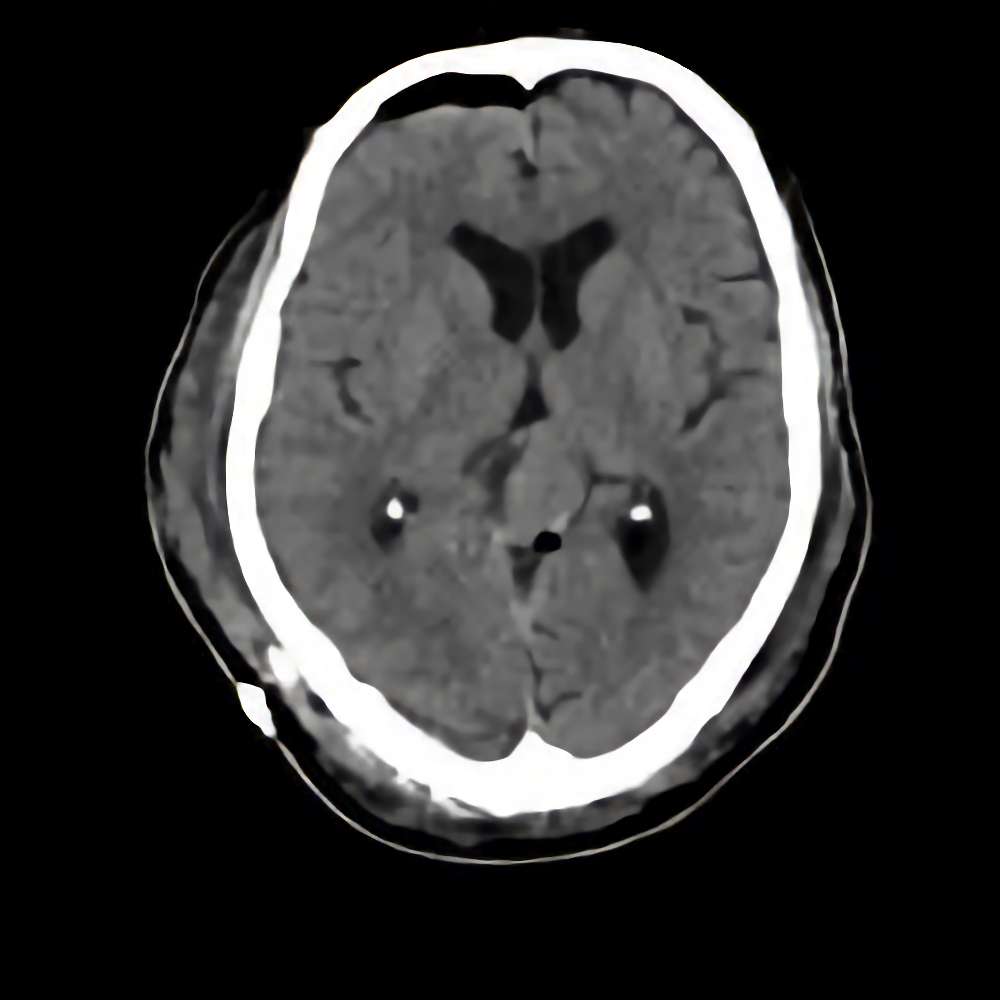

松果体腫瘍

断層撮影

手術前1

No.’15_5 手術前1

No.’15_5 手術後